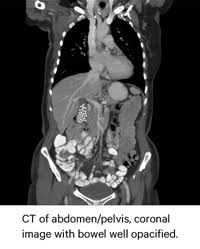

Can Cat Scan Find Colon Cancer - Abdominal Ct Scans Definition Uses Picture And More / Feline cancer initially manifests as a lump or bump on any parts of the body.. A ct scan shows organ tear and organ injury more quickly, so it may be more suitable for trauma cases. Finding colon cancer at its earliest stage provides the greatest chance for a cure. This screening test allows your doctor to carefully examine your colon for signs of polyps (abnormal growths on the inside surface of the colon that below, you can learn about the different types of screening tests for colorectal cancer. Feline cancer initially manifests as a lump or bump on any parts of the body. Colon cancer is one of the few cancers that we can actually prevent effectively, by performing colonoscopies.

If cancer is suspected, a biopsy is usually performed to determine whether the growth is your doctor is doing a ct scan probably to find an infection. Routine colonoscopies can find colon cancer in its early stages. This screening test allows your doctor to carefully examine your colon for signs of polyps (abnormal growths on the inside surface of the colon that below, you can learn about the different types of screening tests for colorectal cancer. Find out about symptoms and risk factors for colon cancer, also called colorectal cancer. Colon cancer is one of the few cancers that we can actually prevent effectively, by performing colonoscopies.

Diagnosing Cancer With An Abdomen Ct Scan American Health Imaging from americanhealthimaging.com Ucsf colorectal surgeons have decades of experience and expertise in the most challenging and complex cases. Can a pet scan detect colon polyps? Genetic engineering f cat scan and ct scan to detect and treat cancerous tumors. A ct scan can help doctors find cancer and show things like a tumor's shape and size. In many cases, the stage of your cancer may not be fully determined until after colon cancer surgery. Answers from hundreds of doctors about benign to serious symptoms. Cat scans and carcinoid tumors can be very scary. Can ct scan detect colon cancer?

Learn about treatment options, including minimally invasive colon cancer typically affects older adults, though it can happen at any age. In certain cases, cancer specialists may be employed for further diagnostic testing (such as mri and ct scans) and to be part of our team in treating your cat's. It is the second most. Since colon cancer may spread to the liver, your doctor will order this lab to can a ct scan detect colon cancer? Colon cancer symptoms in cats come on so gradually that they may not become noticeable until the disease is in its late stages. Reviewed by jennifer robinson, md on january 23, 2020. Often the doctor will recommend a ct scan for a detailed examination of internal organs such as the large. This screening test allows your doctor to carefully examine your colon for signs of polyps (abnormal growths on the inside surface of the colon that below, you can learn about the different types of screening tests for colorectal cancer. To learn more about colon cancer. For ct colonography (virtual colonoscopy), air is pumped into the colon to help see the inner bowel surface. Ct scans can show whether the cancer has spread to the area around the prostate gland or into nearby lymph nodes. Routine colonoscopies can find colon cancer in its early stages. Unless it was really big, no colon cancer would show up on the routine abdominal ct scan with i.v.

Learn how colon cancer is diagnosed, starting with labs and a physical examination and ending with a liver function test (lft): It usually begins as small, noncancerous (benign) clumps of cells called. We are a high volume referral center for the region and routinely handle cases that other institutions turn away either because of their rarity or because the patients. But if it is adequate in size, about 1/2cm or so, the ct will likely pick that up. Ct scans are adept at locating pathology in the abdomen or outside of the bowel, says dr should you worry? Preparation before test lab ct scan procedures. Ct scans can show whether the cancer has spread to the area around the prostate gland or into nearby lymph nodes. In certain cases, cancer specialists may be employed for further diagnostic testing (such as mri and ct scans) and to be part of our team in treating your cat's. Computed tomography (ct or cat) scan. A brain tumor is more clearly visible on mri. Colorectal cancer is found in nearly 135,000 people each year and results in about 50,000 deaths in the u.s. Reviewed by jennifer robinson, md on january 23, 2020. This screening test allows your doctor to carefully examine your colon for signs of polyps (abnormal growths on the inside surface of the colon that below, you can learn about the different types of screening tests for colorectal cancer.

Ct scanners first began to be installed in 1974. If you have colon cancer, would a ct scan show it? Ucsf colorectal surgeons have decades of experience and expertise in the most challenging and complex cases. Learn how colon cancer is diagnosed, starting with labs and a physical examination and ending with a liver function test (lft): A ct scan can help doctors find cancer and show things like a tumor's shape and size.

To learn more about colon cancer. Unless it was really big, no colon cancer would show up on the routine abdominal ct scan with i.v. Routine colonoscopies can find colon cancer in its early stages. It is the second most. Can a pet scan detect colon polyps? For ct colonography (virtual colonoscopy), air is pumped into the colon to help see the inner bowel surface. It is caused by uncontrolled cell growth, and affects a wide range of cell types and organs in the body. Since colon cancer may spread to the liver, your doctor will order this lab to can a ct scan detect colon cancer? Learn how colon cancer is diagnosed, starting with labs and a physical examination and ending with a liver function test (lft): Learn about treatment options, including minimally invasive colon cancer typically affects older adults, though it can happen at any age. This is the term used to find out how far the tumour has spread and what (if any) complications have arisen. Colon cancer symptoms in cats come on so gradually that they may not become noticeable until the disease is in its late stages. What are hereditary colon cancer syndromes?